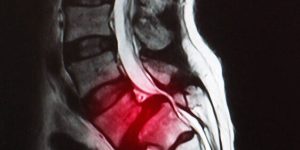

La hernia discal ocurre cuando el material del disco intervertebral presiona los nervios cercanos. El Dr. Valle alivia el dolor y recupera la movilidad mediante tratamientos avanzados.

Es el estrechamiento del canal vertebral que comprime la médula espinal o los nervios. El doctor ofrece soluciones efectivas para reducir la presión y mejorar la calidad de vida.